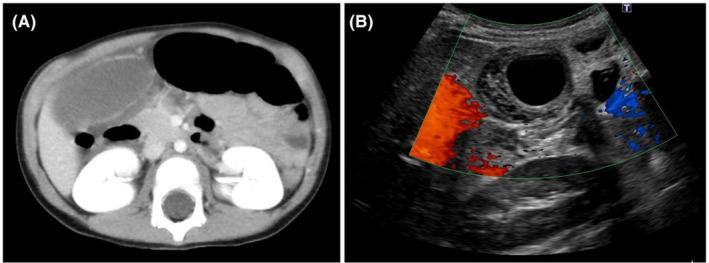

A 3-year-old boy with abdominal pain and vomiting was admitted to our hospital. He was diagnosed with acute cholecystitis through abdominal ultrasound and computed tomography, and he received antibiotics. Two days after admission, a repeat abdominal ultrasound revealed exacerbation of gallbladder wall thickness and lack of intramural blood flow, which led to a diagnosis of gallbladder torsion. Emergency laparoscopic cholecystectomy was performed, and the gallbladder was twisted counterclockwise at 270°. After an uneventful course of intraoperative and postoperative treatment, the patient was discharged on postoperative day 6.

一名3岁腹痛伴呕吐男孩入住我院。通过腹部超声和计算机断层扫描诊断为急性胆囊炎,并接受了抗生素治疗。入院两天后,重复腹部超声显示胆囊壁厚度增加且壁内血流缺失,从而诊断为胆囊扭转。进行了急诊腹腔镜胆囊切除术,胆囊逆时针扭转270°。经过平稳的术中及术后治疗过程,患者于术后第6天出院。